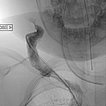

Aufgrund der fehlenden Rückbildung, wahrscheinlich auch durch die massive Stenose des venösen Abstroms, fällt der Entschluss zur Embolisation des Hämangioms im 24. Lebensmonat zur Induktion einer Regression. Zunächst wird dazu retrograd von transvenös der venöse Abstrom (Vena jugularis externa rechts) kanüliert.

Anschließend wird dann ein kleiner Ballonkatheter eingebracht, der den venösen Abstrom vor einer Embolisation blocken soll und damit eine Embolisatverschleppung vermeiden soll.